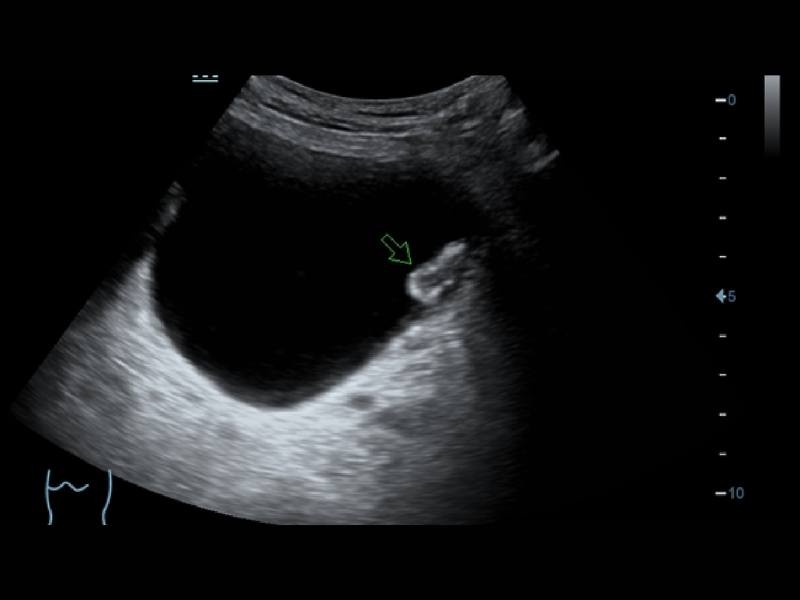

Em combinação com a exclusiva tecnologia 3T da Mindray (combinação de três camadas, design de corte total, controle térmico), os otimizados transdutores convexos, com feixe em fases e volume oferecem uma cobertura de aplicação mais extensa, resultando em uma excelente solução de varredura nas áreas de ABD, cardiologia, obstetrícia/ginecologia, entre outras.